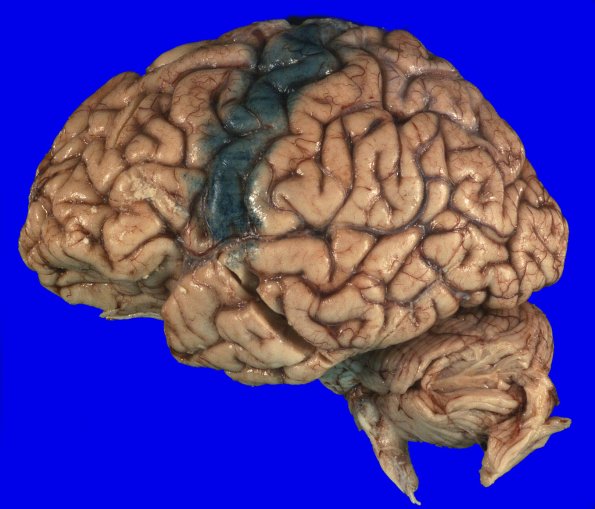

The lateral aspect of the cerebral hemispheres viewed fresh (14A1) and fixed (14A2). The fixed section shows dye applied before sectioning in order to make it easier to locate the precentral gyrus in a coronal slice.